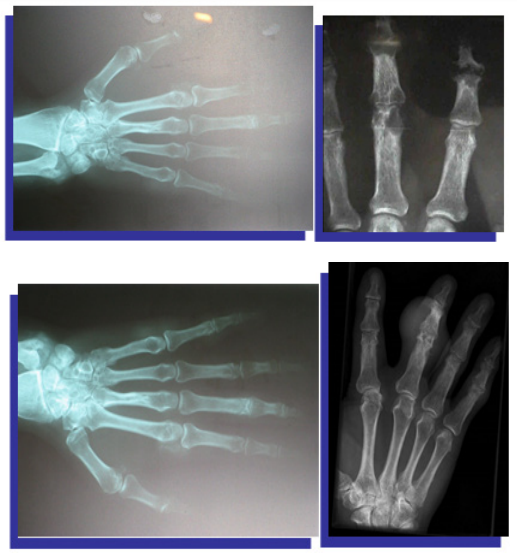

Plain radiographs (Figure 4) (Figure 5)

Figure 4 X-ray of both hands shows eccentric juxta-articular soft tissue nodule associated with adjacent bony erosion (rat-bite erosion) with sclerotic margins and overhanging edges invoking the proximal interphalangeal joint of middle finger with normal bone mineralization.

Figure 5 X-ray of both hands shows eccentric juxta-articular soft tissue nodule associated with adjacent bony erosion (rat-bite erosion) with sclerotic margins and overhanging edges invoking the proximal interphalangeal joint of middle finger with normal bone mineralization.

1. Plain radiographs may show some like soft tissue swelling but these findings are inconsistent with gout, therefore not diagnostic, otherwise, most very early plain imaging is usually no findings!

2. Recurrent flares and Chronic gout might show:

3. Plain radiologic changes occur characteristically in the chronic stage, some may show these changes though not all patients progress to this. There is commonly a predilection for the small joints of the hands and feet.

Joints

1. An early sign is the presence of joint effusion

2. intact joint space until late disease

3. an absence of periarticular osteopenia

4. eccentric erosions

5. the typical appearance is the presence of well-defined “punched-out” erosions with sclerotic margins in a marginal and juxta-articular distribution, with overhanging edges

Bones

1. punched-out lytic lesions

2. Overhanging sclerotic margins

3. osteonecrosis

4. Mineralisation is normal